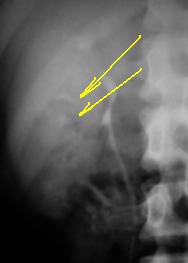

20 минута с выведением правого крестцово-подвздошного сочленения

Изображение

Считаю, что достоверных рентгенпризнаков сакроилеита нет. Для туберкуллеза сакроилеит не вполне характерен. Снимок правого крестцово-подвздошного сочленения неправильный: снят с приподнятым левым боком, так снимают левое сочленение, да и  то недостаточно повернут (ориентир - дугоотросчатые суставы соответствующей стороны). Если речь идет о патологии мочевого пузыря - боковой снимок обязателен.